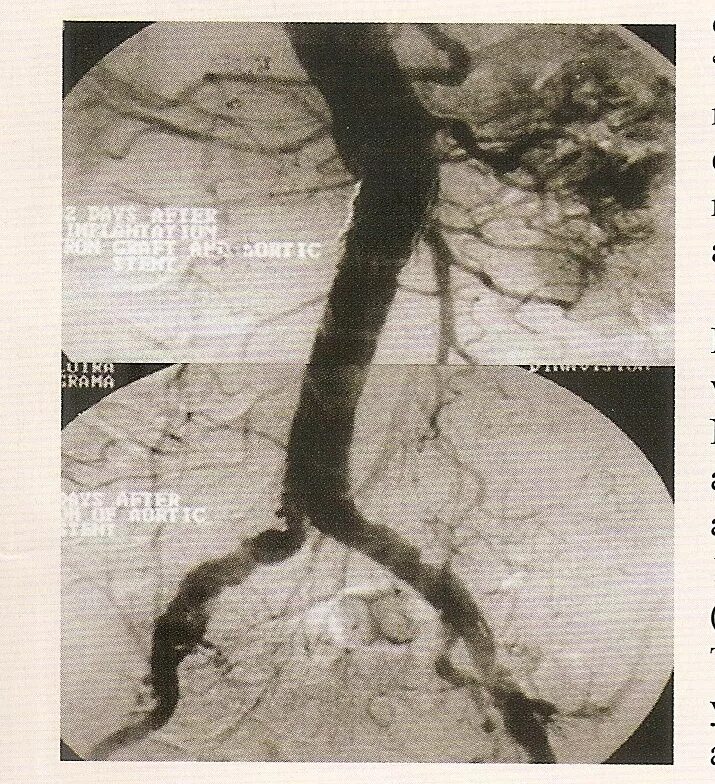

Кальциноз брюшного отдела